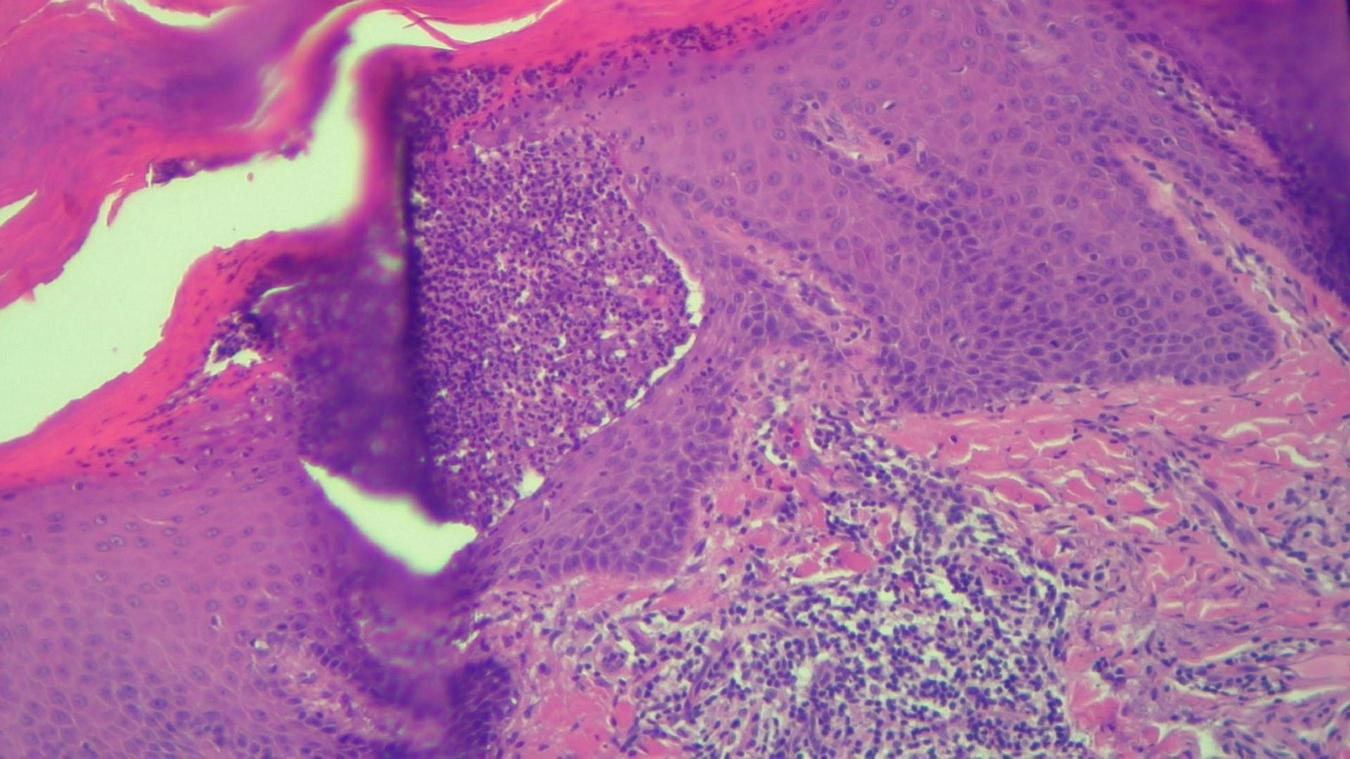

FIGURE 7

HEx100—Another skin biopsy aspect of the same patient with Kogoj pustule.

The histopathological examination revealed (Figures 5–8). The examined skin fragment reveals an epidermis with marked hyperkeratosis, both ortho- and parakeratosis (confluent, with accumulations of neutrophils at this level—Munro microabscesses), a granular layer of variable thickness, with hypergranulosis and agranulosis, Kogoj pustules, regular psoriasiform acanthosis with elongated epidermal ridges, some rounded at the ends and fused at this level. The superficial dermis shows congested blood vessels, some with a tortuous appearance, and a perivascular inflammatory infiltrate consisting of lymphocytes, histiocytes, neutrophils (minimal), and extravasated red blood cells. Areas of erythrocyte exocytosis are also observed at the epidermal level.